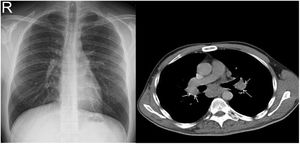

CXR-based staging of sarcoidosis was developed before the introduction of CT, and for decades, it has been the gold standard for staging, follow-up and prognosis of pulmonary sarcoidosis.14 It was preferential method because of low price, low radiation exposure and wide use as well. However, the intensity of symptoms, the presence of extrapulmonary disease, the results of pulmonary function tests, and the necessity of treatment are not well correlated with CXR.15 CXR is insufficient to portray small parenchymal abnormality in early stages of the disease, and small mediastinal and hilar lymphadenopathies. The study showed that there was no correlation between lung function tests (FVC, FEV1 and DLCO) and CXR imaging and it is not a reliable test to detect pulmonary exacerbations of sarcoidosis.16 CT scans are more sensitive than CXR in detecting lung parenchymal changes in sarcoidosis. High-resolution CT (HRCT) can reveal ground-glass opacities, nodules, and peribronchovascular thickening. CT can help in assessing disease extent and severity, guiding treatment decisions, and monitoring disease progression. Unlike X-ray scans, some CT lesions demonstrate a relationship with pulmonary function tests.17 Drent et al. demonstrated correlations between respiratory functional tests and CT features such as thickening of the bronchovascular bundle, intraparenchymal nodules, septal and non-septal lines, or focal pleural thickening.18 Zappala et al. have suggested that compared with CXR presentations, CT scan appear to be more consistent with pulmonary functional changes.19 CT is significantly more sensitive than CXR regarding detection of early sarcoidosis lesions, which may help us for early decision treatment. This is true even in stage 1/2, which is linked with a favorable long-term prognosis. Despite these facts, the predictive significance of CT findings has not yet been subjected to a significant amount of research. Even among chest radiologists, there is considerable heterogenicity and subjectivity in the interpretation of CXR. Baughman et al. evaluated the discrepancy between two chest radiologists initial assessments of Scadding staging using data from a clinical trial.20 Overall, the authors discovered only fair interobserver concordance, and with regards to the presence of fibrosis, they found only fair interobserver concordance. They also mentioned that it was hard to tell if a patient was at stage II or stage III because chest radiologists could not agree on the appearance of hilar lymphadenopathy. Zhang et al. compared the chest CT and CXR imaging for staging of pulmonary sarcoidosis using clinical records of 227 sarcoidosis patients.21 They reported that overall, 50.2% patients showed discordant sarcoidosis stage between CXR and CT, which findings support the results from our present study. The primary reason for inconsistent stage between CXR and HRCT was failure to detect mediastinal lymph node enlargement in the shadow of the heart in CXR and small nodules because of the limited resolution of CXR. Also they found more patients with pleural involvement detected by CT (25.6%) compared with CXR (7.5%). In addition, the authors recommend new staging criteria for pulmonary sarcoidosis according to CT imaging, not CXR. Russo et al. investigate the sensitivity and specificity of different chest imaging for sarcoidosis screening in patients with cardiac presentations.22 While the CXR was suboptimal as a screening test, in contrast CT and cardiac/thorax MRI had excellent sensitivity. CT has the highest specificity among imaging modalities. Sarcoidosis primarily affects the upper lung zones, and granuloma are predominantly spread along lymphatics, it is more difficult to assess these regions using CXR and when assessing lesions of this kind, CT is preferable method. CT may also distinguish confluent granulomas, which have a peculiar imaging result known as the “galaxy sign,” which resembles a star cluster when viewed through a telescope.23 CT also may help in the differential diagnosis of sarcoidosis with lymphangitic carcinomatosis, which can present with a nodular perilymphatic pattern and septal thickening. Various studies have demonstrated the superiority of CT in detecting lesions corresponding to fibrosis and in diagnosing more advanced stages of the disease.24 CXR scans revealed fibrosis in 5–10%, whereas CT scans resulted in such changes being described in as many as 20–50% of patients. In fibrotic stage, the presence of “honeycombing” and traction bronchiectasis is associated with worse prognosis, and a larger degree of fibrotic alterations detected on CT scan is known to be predictive of mortality.25 Our research results align with previous studies in the literature. In this investigation, we observed that CT imaging outperforms CXR in terms of early detection and staging of sarcoidosis (Fig. 1). The predominant stages identified through CT examination, which were not visible on CXR, were stage 1 and stage 2 (Fig. 2). Furthermore, CT imaging provided valuable insights into pleural involvement, early alveolitis, and pulmonary hypertension.25 Nevertheless, our study does have certain limitations. Firstly, the data we used was confined to a single center and involved a relatively small number of patients, which restricts the generalizability of our findings to all sarcoidosis patients. Another limitation is that our study population consisted solely of individuals of Caucasian origin, and it is widely acknowledged that disease phenotypes may exhibit significant racial differences. Consequently, it is essential to replicate our findings in a group of African-Americans to ensure their broader applicability. Furthermore, had we enrolled patients consecutively and conducted a prospective evaluation of CXR and CT scans with a larger number of readers, it would have likely minimized potential biases in the results. Despite these limitations, it is worth noting that our findings align closely with those reported in existing literature on the subject.